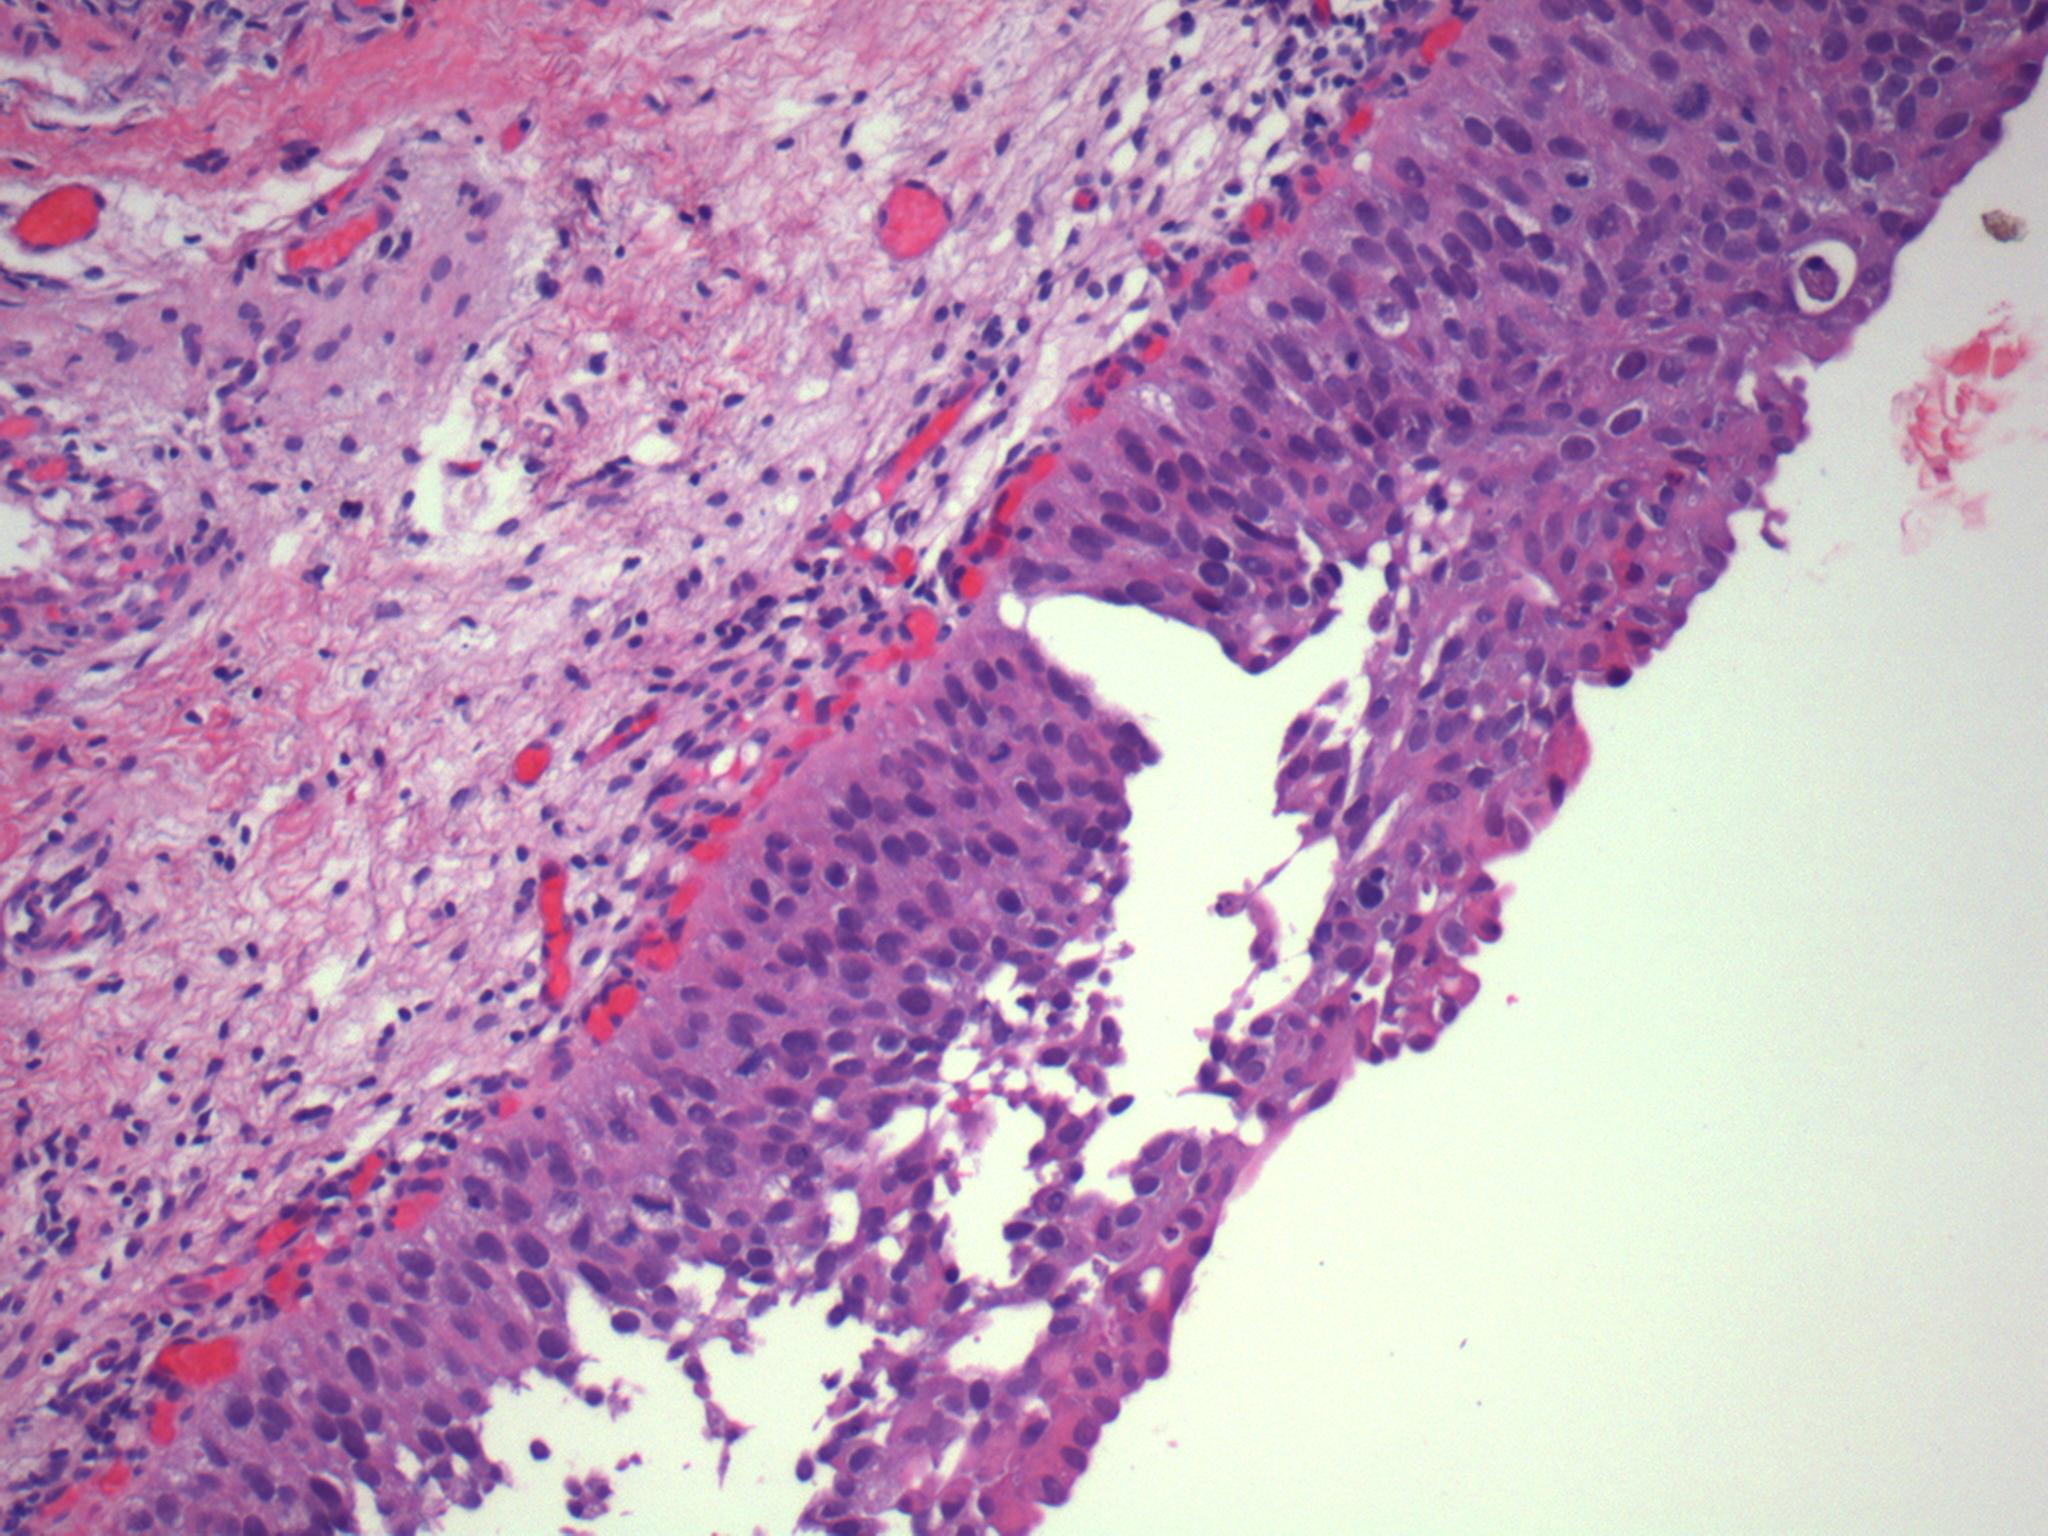

Consensus grade: Carcinoma in situ (CIS)

The urothelium displays loss of cohesion, loss of polarity and prominent pleomorphism.